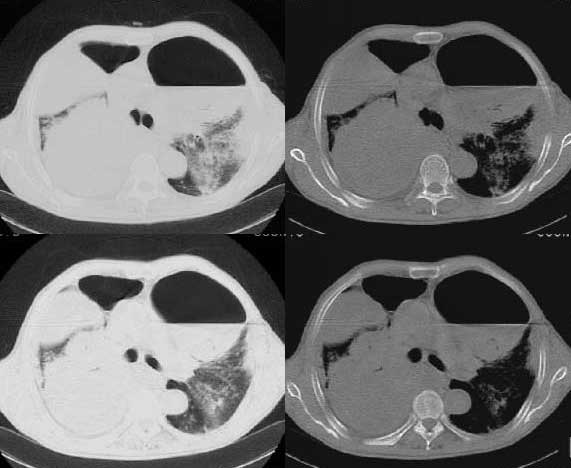

以下是引用woaixct在2006-6-23 12:15:00的发言:[br]第一张胸片示:右肺上叶为大片致密影占据,左肺上见大片致影及空洞性病灶并有液平;[br]第二张胸片示:左肺上叶致密影及空洞性病灶基本吸收,而右肺上叶之病灶有少许吸收改变;[br]ct片示:右上叶大片软组织密度,右肺门区至右肺上叶见巨大软组织块,内见支气管充气征,上纵隔右移,主气管及上叶支气受压变扁,中间支气管狭窄,左肺上叶空洞性病灶并有液平,左肺上叶尖后段见大片致密影,结合2张胸片考虑,ct片是4月份所摄,而不是6月份的片子;[br]结合2张胸片及ct片考虑:[br] 1.右中央型肺癌伴右肺上叶不张;[br] 2.左肺上叶尖后段炎性变及左肺脓肿;[br]第2张胸片提示:经过一个多月的不规则抗炎治疗,左肺上叶病灶及右肺上叶不张病灶基本吸收,而右肺占位无明显变化。

以下是引用jiangjing在2006-6-23 21:21:00的发言:[br]个人考虑还是两肺感染性病变可能大,主支气管及叶支气管是通畅的,并可见支气管气相;ct提示病变是以肺叶分布的,密度相对均匀;胸片可见有叶间裂下坠征,是不是考虑克雷伯杆菌感染可能.病人前后两张片比较病变是增多[应该考虑混合感染可能性大,右肺癌待排建议查痰及穿刺检查]